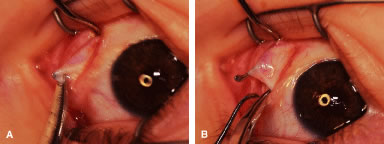

RECESSION PROCEDURE: LIMBAL APPROACH

Two 6-0 silk stay sutures are passed through the conjunctiva and superficial scleral tissue at the limbus (see Fig. 49). These sutures are used to stabilize the globe during the procedure. These stabilizing sutures attached to bulldog clamps will hold the globe in adduction or abduction as required.

A no. 15 surgical knife or other similar instrument is used to penetrate the conjunctiva at the limbus (Fig. 50). Care is taken to approach the limbustangential to the globe so that inadvertent penetration of the sclera or cornea is avoided. A Westcott scissors also may be used to incise the conjunctiva at the limbus. To facilitate this step, conjunctiva is lifted gently with a 0.5-mm Castroviejo forceps (see Fig. 50).

|

A blunt-tipped Westcott scissors is used to extend the incision for about 3 clock hours (Fig. 51). Once the fused area of conjunctiva and anterior Tenon's capsule has been penetrated, blunt dissection is performed to carry the limbal incision back toward the muscle. This maneuver is best accomplished by directing the closed tips of a blunt-tipped Westcott scissors into the tissue and letting them open to spread the tissue in a plane between the scleral surface and the underside of Tenon's tissue. The limbal incision is extended radially with a Westcott scissors (Fig. 52). Care is taken to avoid cutting into the anterior portion of the rectus muscle insertion (Fig. 53).

|

|

Figure 54 shows the conjunctiva being elevated by the assistant with Castroviejo forceps. The anterior extension of the muscle can be seen.

|

A Jameson hook is passed under the rectus muscle about 2 mm posterior to the insertion (Fig. 55). The insertion has been identified previously with a Stevens' hook that is used to lift up the tendon to facilitate passage of the Jameson hook.